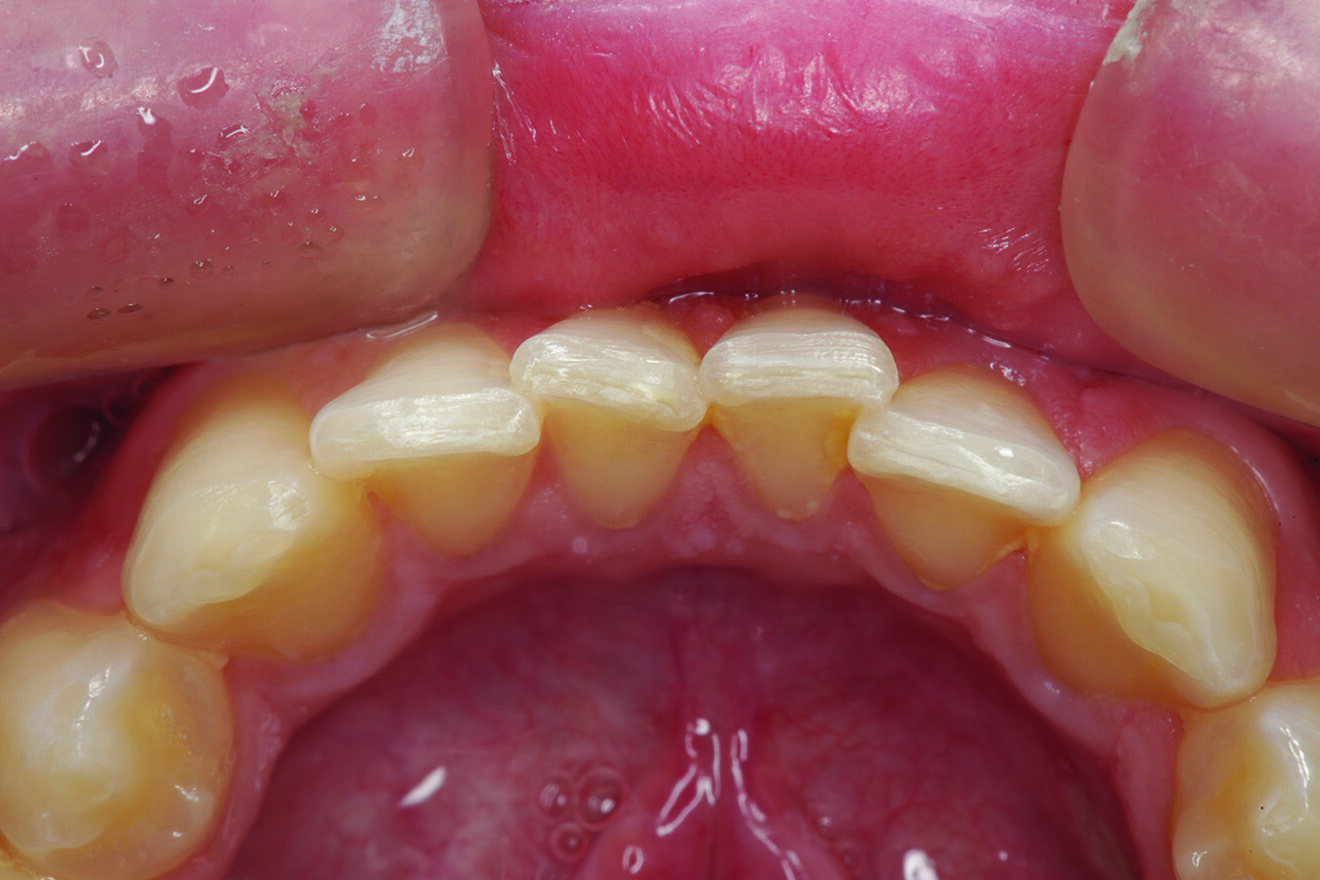

What about the alignment of the opposing teeth? It could be observed that excessive wear was present on the incisal edges of teeth #31 and 41 (Fig. 2). From the incisal view, exten­sive wear was seen on all mandibular inci­sal edges due to occlusal disease—which is often seen yet left untreated (Fig. 3). Tooth #41 was also facially positioned so that in pro­trusive excursion it engaged the palatal surface of tooth #11 prematurely, placing addi­tional stress on both the palatal surface and inci­sal edge of tooth #11 before coupling with the remainder of the maxillary anterior segment. This demonstrates that addressing these issues restoratively involves more than just fixing a chipped composite restoration.

Fig. 2: Teeth in protrusive excursion, showing excessive wear on the tooth (# 41) opposing tooth #11, indicating hyperfunction and increased functional stress on the restored area.

Fig. 3: Incisal view showing that tooth #41 was the arch form’s most facially positioned mandibular incisor.